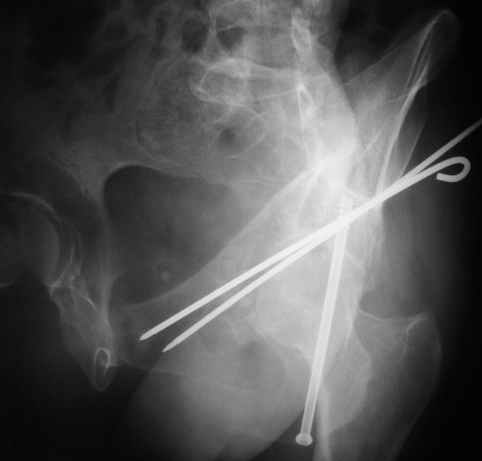

Уважаемые коллеги,Мужчина 36 лет от роду попал в ДТП 24.08.04 Рентгенограммы в приложении.

Диагноз- перелом с вовлечением таза, разрыв правого сакро-илиак сочленения vertical shear injury, перелом крыла подвздошной кости?, перелом ацетабулум Т type или Both column?, перелом шейки бедра, перелом проксимального отдела бедра.

перелом крыла правой подвздошной кости, перелом обеих колонн вертлужной впадины, двусторонний перелом лонных костей (С2.2) повреждение передних связок правого крестцово-подвздошного сочленения,

ипсилатеральный перелом шейки и диафиза бедра.